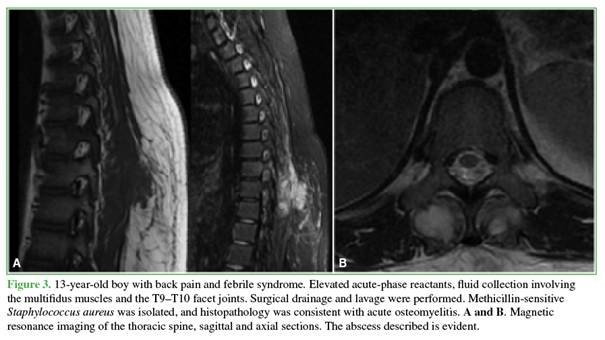

seven patients (p = 0.001), including four cases of MRSA and three of MSSA (Figures 3-6).

Magnetic

resonance imaging showed hypointense signal on T1-weighted sequences and

hyperintense signal on T2-weighted and STIR sequences, with gadolinium

enhancement. In patients with bone involvement and negative blood cultures,